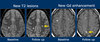

Diagnóstico?

Esclerose concentrica de Balo